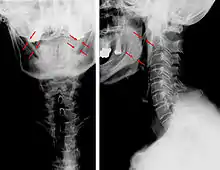

CT scan, coronal section showing bilateral extended styloid process and stylohyoid ligament ossification (incidental finding)

Diagnosis is suspected when a patient presents with the symptoms of the classic form of "Eagle syndrome" e.g. unilateral neck pain, sore throat or tinnitus. Sometimes the tip of the styloid process is palpable in the back of the throat. The diagnosis of the vascular type is more difficult and requires an expert opinion. One should have a high level of suspicion when neurological symptoms occur upon head rotation. Symptoms tend to be worsened on bimanual palpation of the styloid through the tonsillar bed. They may be relieved by infiltration of lidocaine into the tonsillar bed. Because of the proximity of several large vascular structures in this area this procedure should not be considered to be risk free.

Imaging is important and is diagnostic. Visualizing the styloid process on a CT scan with 3D reconstruction is the suggested imaging technique.[12] The enlarged styloid may be visible on an orthopantogram or a lateral soft tissue X ray of the neck.